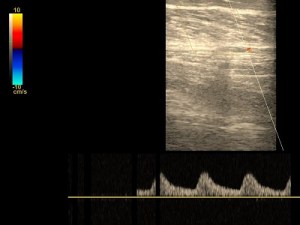

Żyły kończyn dolnych lub górnych

Wykrywa choroby układu żylnego: zakrzepicę, niewydolność zastawek żylnych, etiologię obrzęków, zmiany pozapalne i pozakrzepowe. Badanie żył głębokich i powierzchownych. Jednej lub obu kończyn.

Prawidłowa żyła podkolanowa.